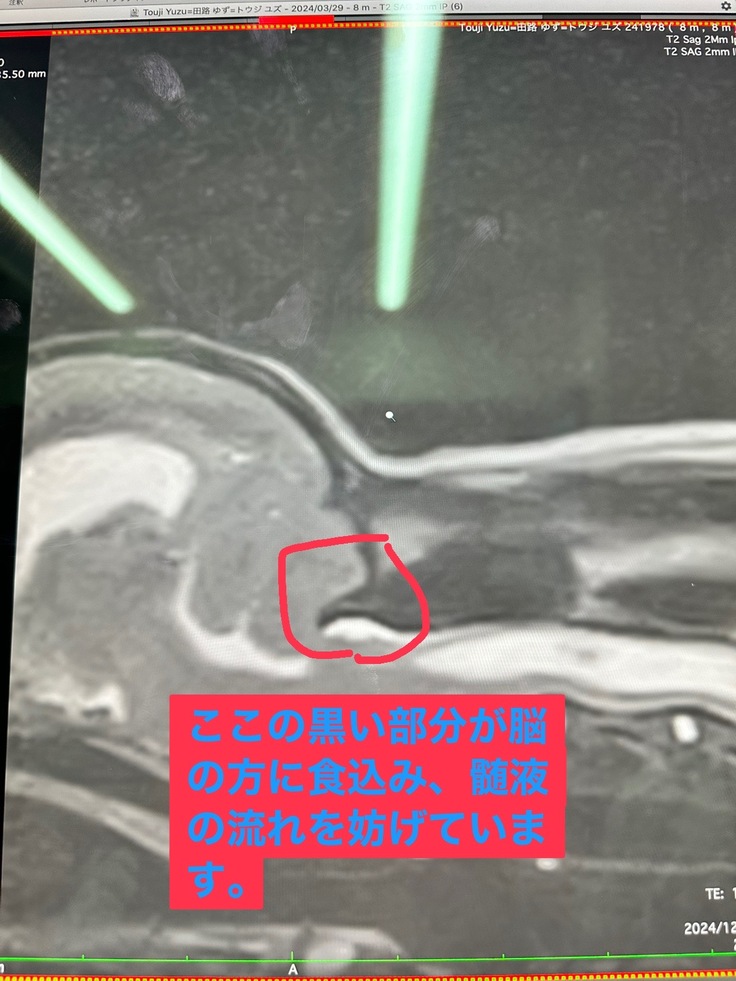

結果、尾側後頭骨形成不全・脊髄空洞症でした。

ゆずの場合、程度が酷くお腹の辺りまで空洞が出来ており、治療を始めて2ヶ月ですが現在の所好転する気配がありません。

完治のない病気で一生付き合っていく事にはなるのですが、現在の投薬治療では改善が見られない為手術を受ける事になりました。

後頭骨の一部を削り、髄液の通りを良くする手術です。